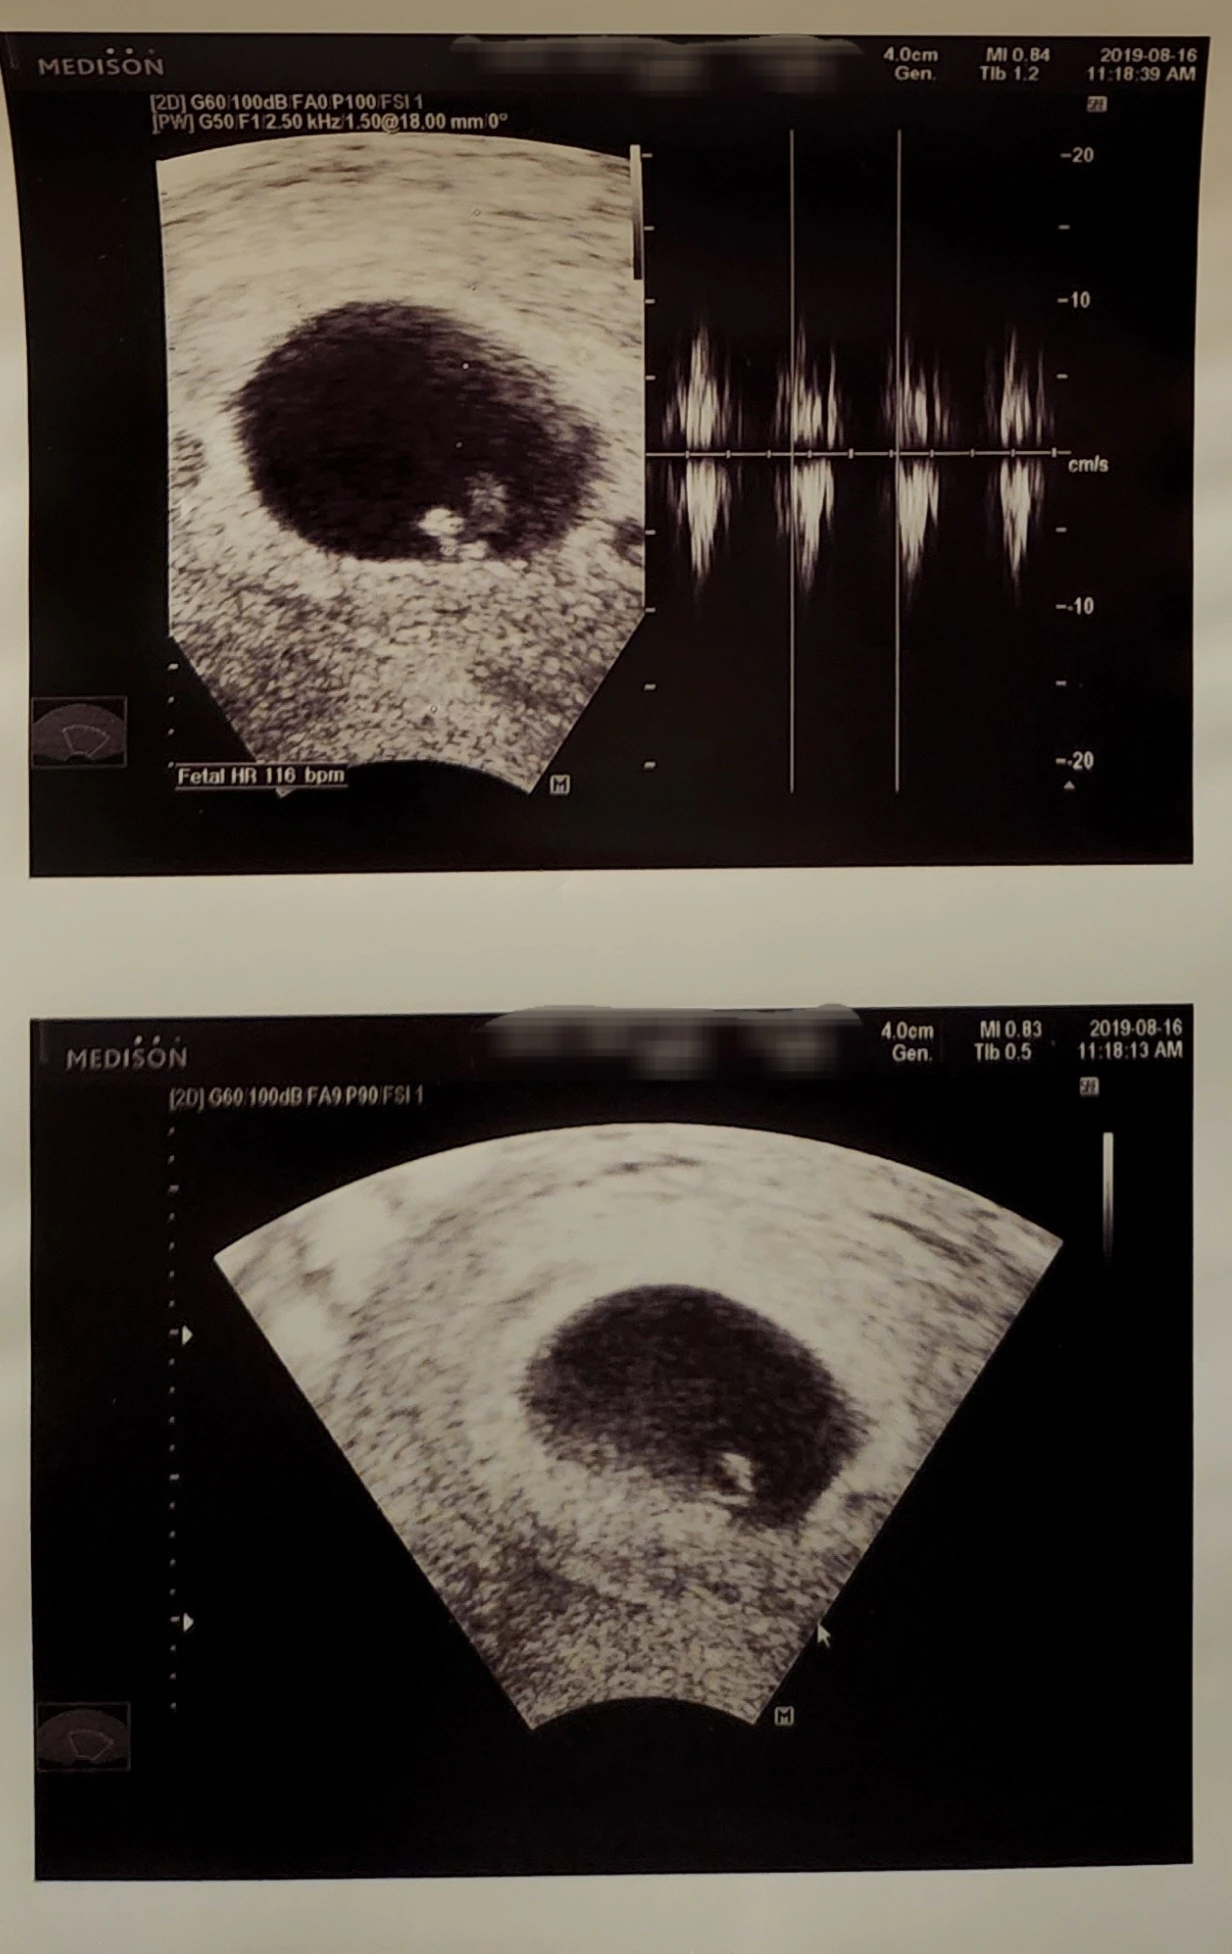

심장이 뛰지 않는데도 초음파 화면 속 양수에서 아무 일도 없다는 듯이 흔들리는 내 첫 번째 아기를 보고 영화 그래비티에서 고요한 우주를 홀로 정처 없이 유영하는 조지 클루니가 생각났다.

의사 선생님은 이미 프린트된 그날의 초음파 사진을 주지 않으려고 했지만 나는 내 첫 번째 아기가 '잊히는 존재'가 아니라 '누군가가 기억해주는 존재'를 만들어주고 싶어서 받아왔고 집에서 그 사진을 끌어안고 하염없이 울다.

둘째이자 태어나기로는 첫째를 임신했을 때 특히 9주까지는 아기가 어떻게 될까 매번 산부인과 검진 시 "심장은 뛰나요?"를 나도 모르게 가장 먼저 물어봤더랬다.